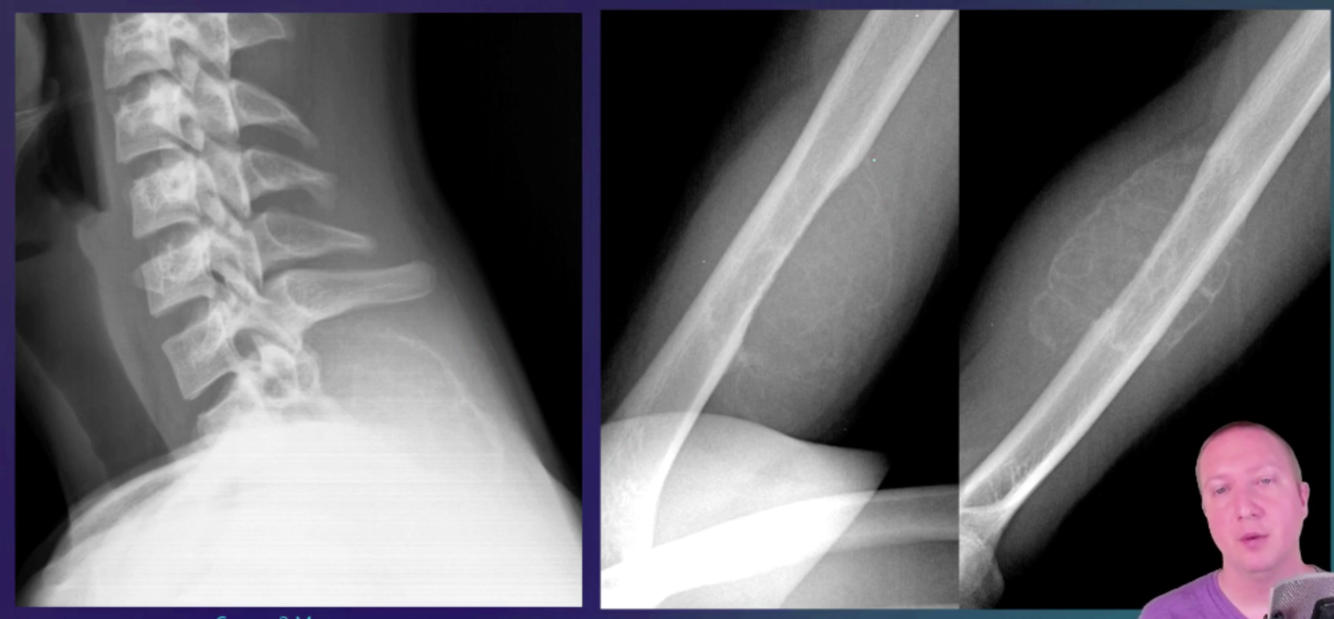

Osteofibrous dysplasia * benign fibro-osseous cortical lesion * occurs almost exclusively in the tibia and fibula. * It is most commonly seen in the mid-diaphysis of the tibia. * Terminology * A commonly used synonym is ossifying fibroma of the long bones. * Epidemiology * most common in younger patients, e.g. ~ 10 years of age * less commonly reported in older patients, up to 63 years of age 3 * slight male predilection (3:2 ratio 3) * Clinical presentation * Most patients present with pain and swelling, and patients may present secondary to a pathological fracture. * Pathology * Osteofibrous dysplasia is considered as a benign, non-neoplastic condition. Some consider it as part of a spectrum of osteofibrous dysplasia-like adamantinoma and adamantinoma. * Microscopic appearance * Histology shows trabecular bone woven within fibrous stroma with osteoblastic rimming and mature lamellar bone. * It is closely related to fibrous dysplasia (fibrous dysplasia is predominantly medullary), but the zonal phenomenon and osteoblastic rimming of bony trabeculae are absent in fibrous dysplasia. * Osteofibrous dysplasia and ossifying fibroma of the jaw have similar histological characteristics, but osteofibrous dysplasia shows cytokeratin-positive cells, whereas ossifying fibroma of the jaw shows psammomatous calcification, which are exclusive features. * Although adamantinoma can contain osteofibrous dysplasia-like components, nests or strands of an epithelioid cell are the differentiating feature between adamantinoma and osteofibrous dysplasia. * Adamantinoma with scarce epithelioid component and mostly composed of osteofibrous dysplasia-like tissue are considered as osteofibrous dysplasia-like adamantinoma. * Radiographic features * Osteofibrous dysplasia is classically a lytic lesion centred in the tibial cortex, often with sclerotic margins. * Because of its similarity to adamantinoma, a much more aggressive pathology, a primary issue is differentiating between the two. * Due to intralesional heterogeneity, needle biopsy may result in diagnostic misclassification, particularly with underestimation of aggressive lesions. Thus, radiologic-pathologic correlation is important with benign or equivocal biopsy results 3. * Osteofibrous dysplasia tends to be: * smaller (mean 6-7 cm versus 10-17 cm for adamantinoma) * with more distinct margins * less likely to involve the medullary cavity * Plain radiograph * Plain radiograph remains the initial and chief investigation. * location: * along long axis: mid-diaphysis, especially anteriorly * along transverse axis: cortical with medullary encroachment * consistency * lucent or ground-glass * lobular-to-bubbly in appearance * margins * narrow zone of transition * sclerosis common * no nidus * no aggressive periosteal reaction * benign-appearing periosteal reaction is non-specific, and can be seen in all lesions along the osteofibrous dysplasia/adamantinoma spectrum 3 * +/- pseudotrabeculation and anterior bowing * MRI * MRI is helpful in evaluation of suspected osteofibrous dysplasia, particularly to evaluate the extent of intramedullary involvement. Complete medullary cavity involvement is more suggestive of adamantinoma. * T1: intermediate signal * T2: intermediate-to-high signal * T1C+: diffuse and intense enhancement. * +/- soft tissue component (non-specific) * can be seen in all lesions along the osteofibrous dysplasia/adamantinoma spectrum 3 * no aggressive cortical destruction * Treatment and prognosis * Surgery is reserved for lesions that are large or demonstrate aggressive behaviour. * They usually have an excellent prognosis and usually, stabilise or spontaneously regress once the child is over 10 years old. * It can be locally destructive and may result in pathological fracture, subsequently pseudarthrosis. * Local recurrences can occur after surgery with some aggressive recurrence, possibly due to components of adamantinoma or possible transformation to adamantinoma. * Differential diagnosis * Consider * ossifying fibroma * adamantinoma * osteofibrous dysplasia-like adamantinoma * intracortical fibrous dysplasia